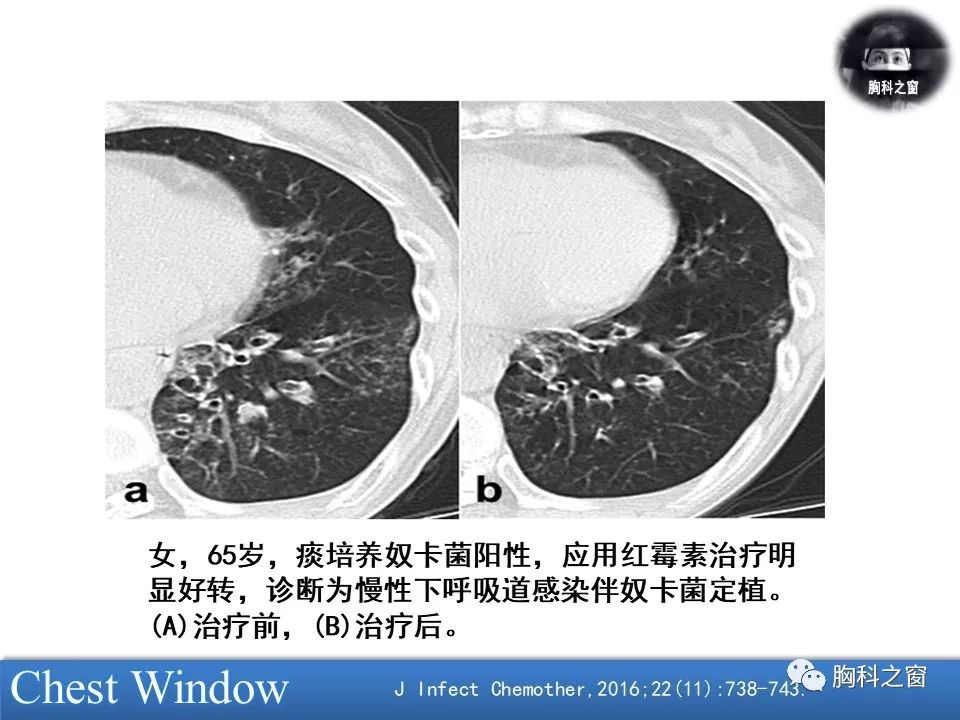

肺奴卡菌病的临床与影像

图片尺寸960x720